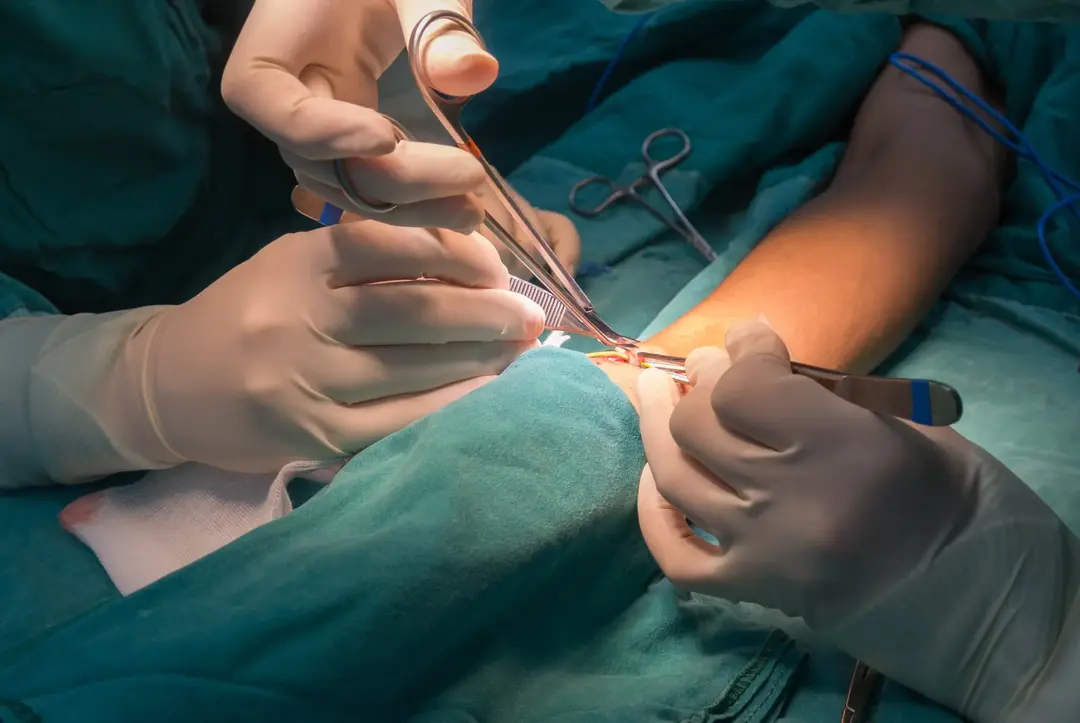

Caso muito interessante publicado no NEJM ([link](https://www.nejm.org/doi/full/10.1056/NEJMicm2206513)). Trata-se de uma mulher de 52 anos em tratamento de diálise peritoneal há 12 anos, apresentou quadro de **dialisato sanguinolento há 1 mês**, negava febre ou dor abdominal. Possui histórico de três episódios de peritonite bacteriana.

Realizado **TC de abdome** mostrou extensa calcificação do peritônio visceral e parietal (imagem A). Devido forte suspeita de **peritonite esclerosante encapsulante** foi realizado laparoscopia exploratória para confirmação diagnóstica. Pode-se observar um peritônio parietal muito espessado coberto por depósitos calcificados (imagem B). Aderências entre o peritônio e serosas inflamadas podem ser observadas.

O exame histopatológico mostrou fibrose e calcificação do peritônio parietal, sendo então confirmado o diagnóstico final de peritonite esclerosante encapsulante com extensa calcificações.

A peritonite esclerosante encapsulante é uma complicação rara da diálise peritoneal, envolve fibrose peritoneal. Em estágios tardios, as alças intestinais podem ficar encapsuladas, levando à obstrução intestinal.

O cateter peritoneal do paciente foi removido e a paciente transferida para o programa de hemodiálise.